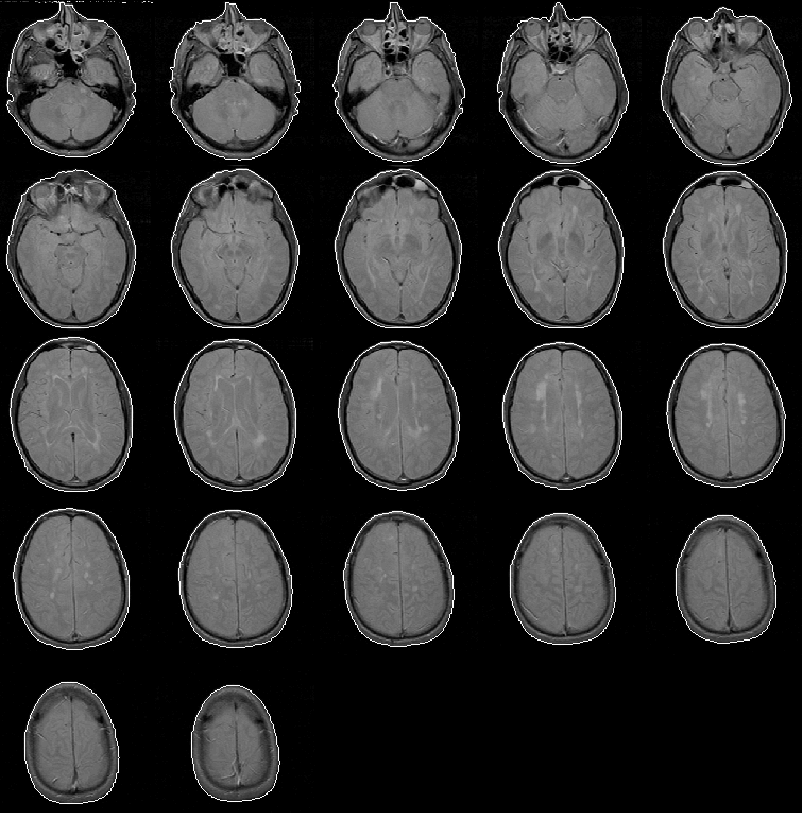

The head mask for Data Set 5 is overlaid on the PD-weighted volume in Figure 8.10. The mask contains minor errors similar to those in the head mask of Data Set 2.

Figure 8.10: The head mask for MRI Data Set 5 overlaid on the PD-weighted scan.